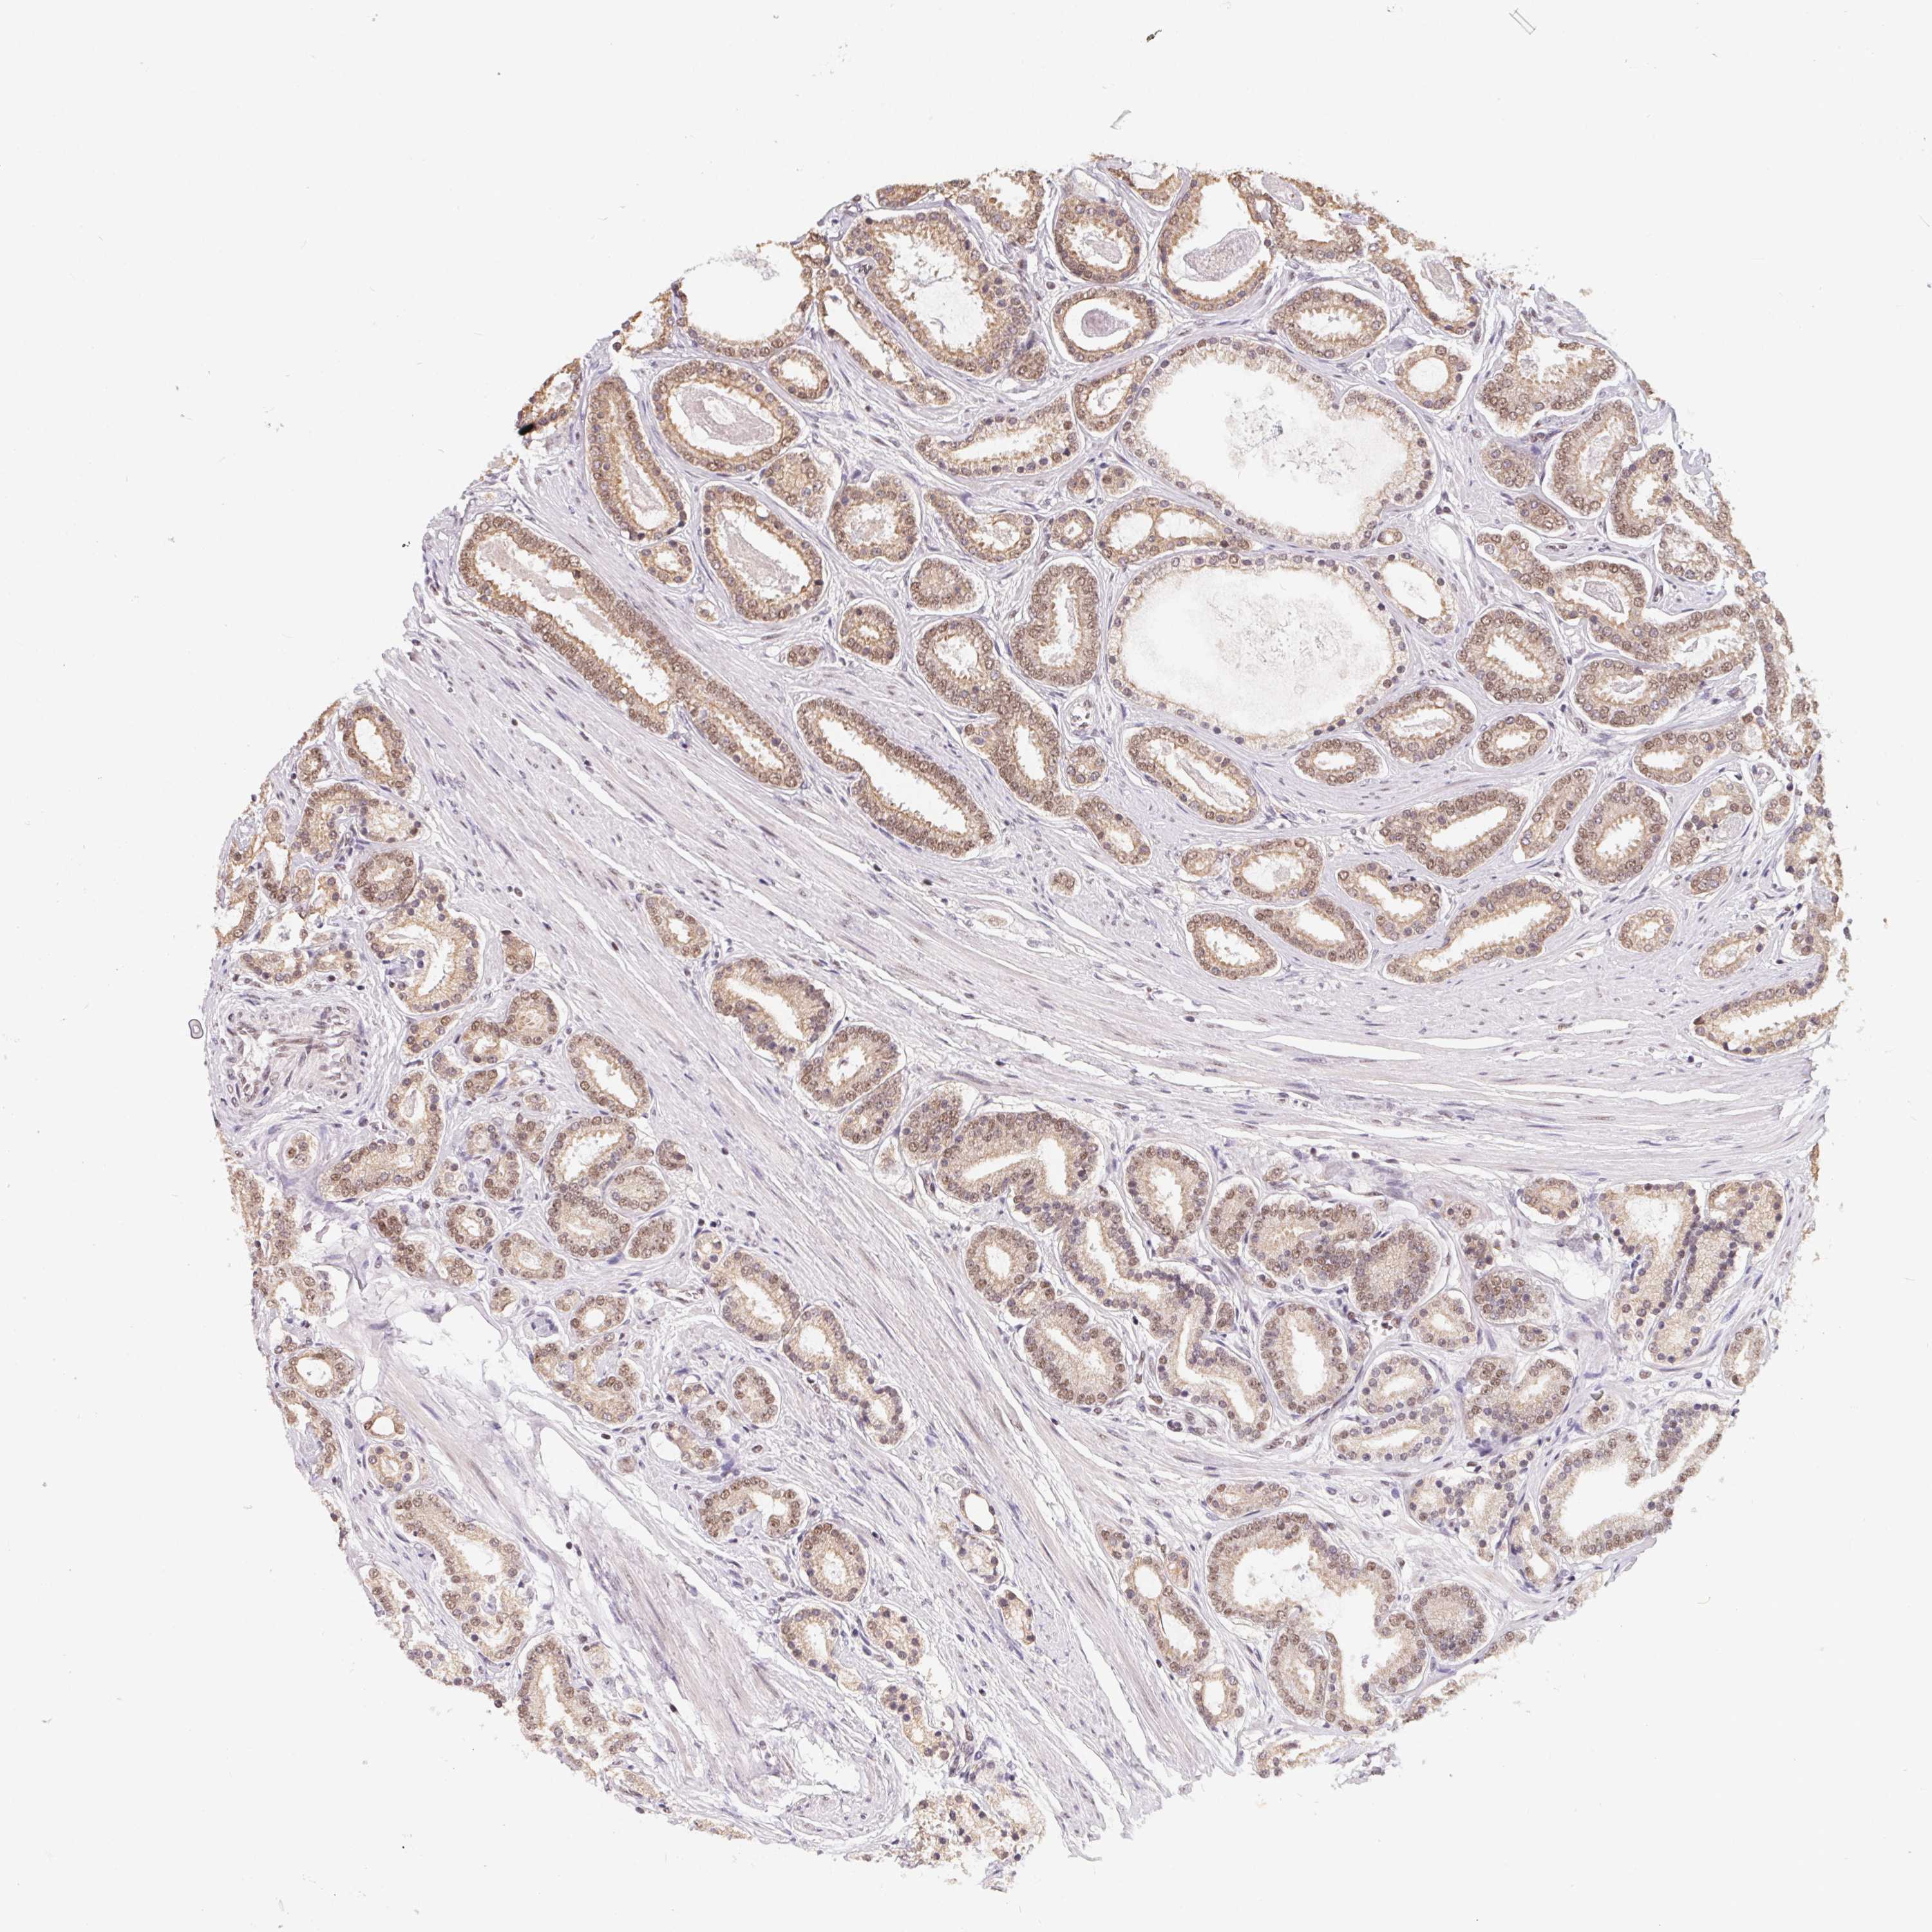

PROSTATE CANCER - Protein expressioni

A mouse-over function shows sample information and annotation data. Click on an image to view it in a full screen mode. Samples can be filtered based on level of antibody staining by selecting one or several of the following categories: high, medium, low and not detected. The assay and annotation is described here.

Antibody stainingi

Antibody staining in the annotated cell types in the current human tissue is reported as not detected, low, medium, or high, based on conventional immunohistochemistry profiling in selected tissues. This score is based on the combination of the staining intensity and fraction of stained cells.

Each image is clickable and will lead to virtual microscopy that enables deeper exploration of all samples and also displays staining intensity scores, fraction scores and subcellular localization as well as patient and tissue information for each sample.

Antibody HPA064854

Staining

High

Medium

Low

Not detected

Intensity

Strong

Moderate

Weak

Negative

Quantity

>75%

75%-25%

<25%

None

Location

Nuclear

Cytoplasmic/membranous

Cytoplasmic/membranous,nuclear

Adenocarcinoma, High grade

Adenocarcinoma, Medium grade

Adenocarcinoma, Low grade